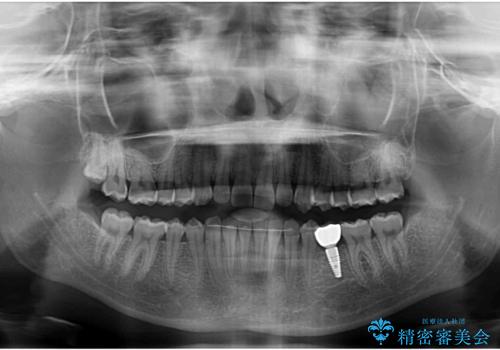

- 前歯の叢生と、奥歯の咬み合わせの悪さを気にして来院された患者様です。

左下には後続永久歯の欠損した乳歯が残存しており、叢生を相まって咬合関係が乱れていました。

乳歯は抜歯し、インビザラインにて矯正治療を行いながら、並行してインプラントによる補綴治療を行うこととしました。

矯正治療が終わるタイミングに合わせてインプラントの埋入を行っていたので、矯正治療を終了すると同時にセラミック補綴治療を行えました。